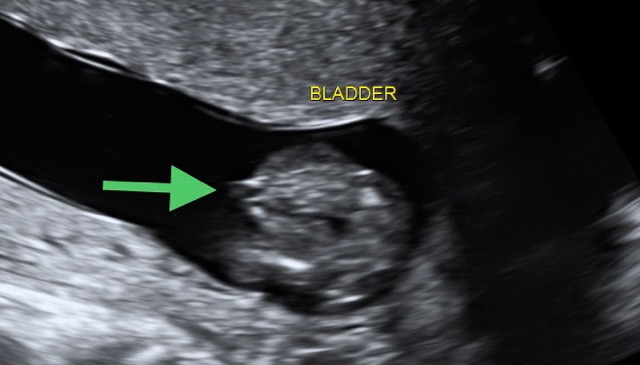

Was looking through my 15 week scan pics and found this pic of the bladder, am I right in thinking those lines where the green arrow is are genitals? Or have I got this completely wrong? Thank you!